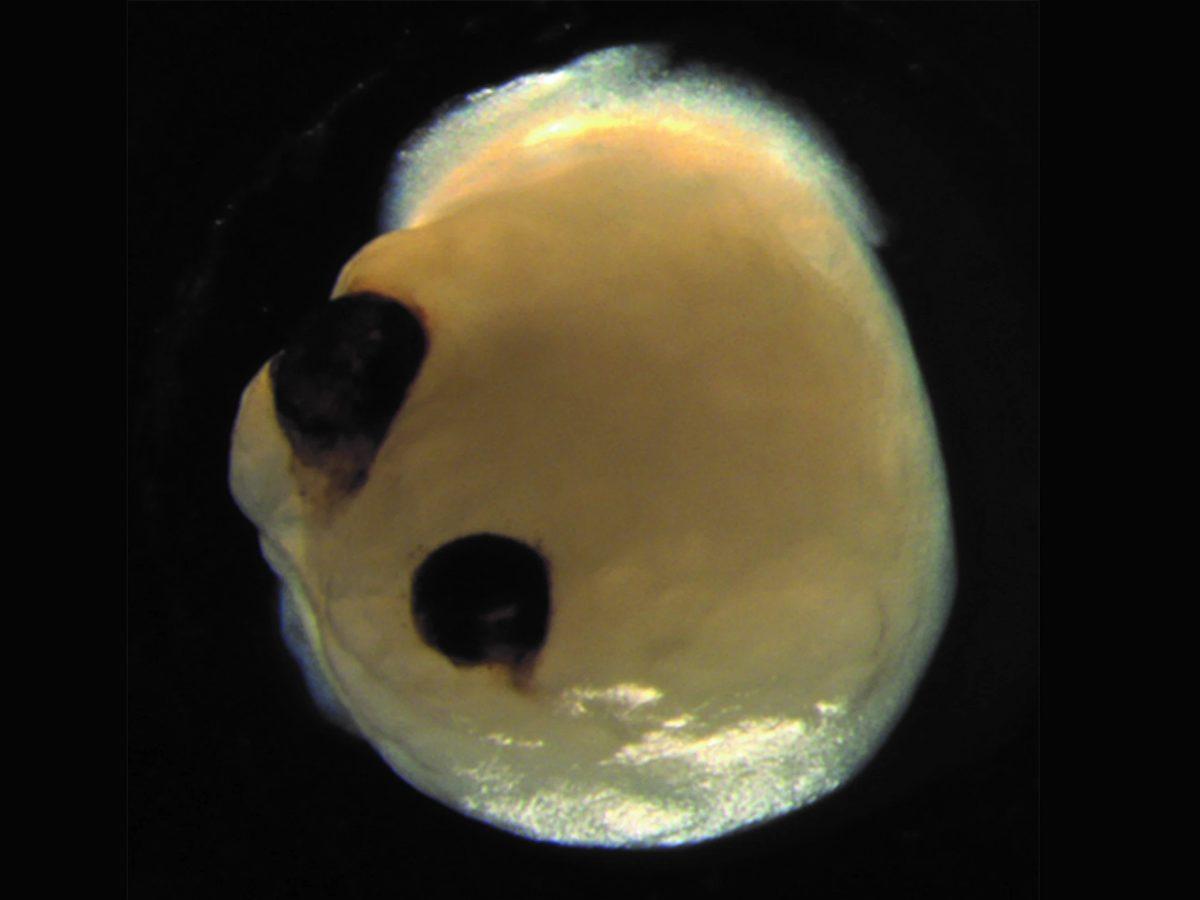

Alman bilim insanları, laboratuvarda kök hücrelerden yetiştirdikleri mini beyinlerde, bugüne kadar bilim camiasının hiç görmediği yeni bir gelişmeye tanıklık etti. Petri adı verilen özel bir bakteri üreme tabağında yetişen bu mini beyinler, kendi kendilerine ilkel göz yapıları geliştirmeyi başardı.

Bilim insanları, göz gelişimini gözlemek adına mini beyinlerin oluşmasında iki farklı hücre kullandı. Bu hücrelerden biri, embriyo gelişimi sırasında tüm göz küresini oluşturmaya yardımcı olan bir kök hücreden oluşuyordu. Dikkatli bir şekilde yetiştirilen beyin organoidleri, tıpkı insan gelişiminde de olduğu gibi 30 gün gibi kısa bir süre içerisinde optik küre oluşturmaya başladı ve bu yapılar, 50. günün sonunda açık açık görülebiliyordu. Organoidlerin oluşturduğu bu optik küre, ışığa tepki verebilen ve hatta lens ve kornea dokusunu içeren sinir ağlarından oluşuyordu.